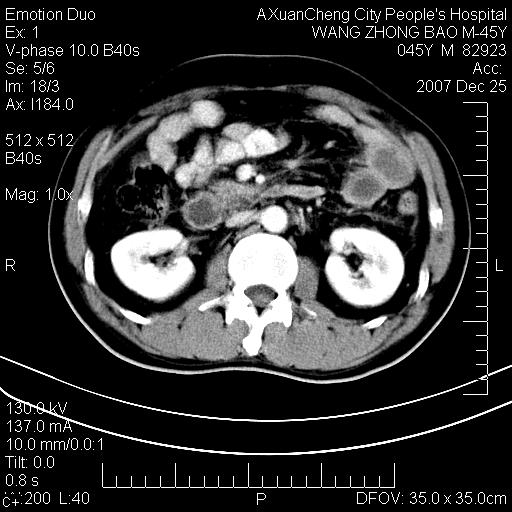

以下是引用qiuleiyu在2007-12-25 18:14:00的发言:[br]胰腺增大,周边渗出改变,肾前筋膜明显增厚,示少量积液.胆囊壁毛糙,周边少许渗出,胆总管壁厚,异常强化,然扩张不明显.结合病程急短;考虑;胆管炎,胆囊炎,胆源性胰腺炎可能大,请结合实验室检查及随访.

以下是引用lisihao在2007-12-25 14:23:00的发言:[br]急性水肿型胰腺炎[br]依据:1、胰腺弥漫性肿大,边缘稍毛糙;[br] 2、双侧肾周筋膜增厚,尤以左侧为甚(重要征象)[br] 3、双侧后胸膜增厚(刺激性炎症);[br] 4、结合病史,查血尿淀粉酶应该可以确诊。